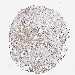

CANCER BREAST CANCER Show tissue menu

BRCA TCGA BRCA VALIDATION PROTEIN EXPRESSION